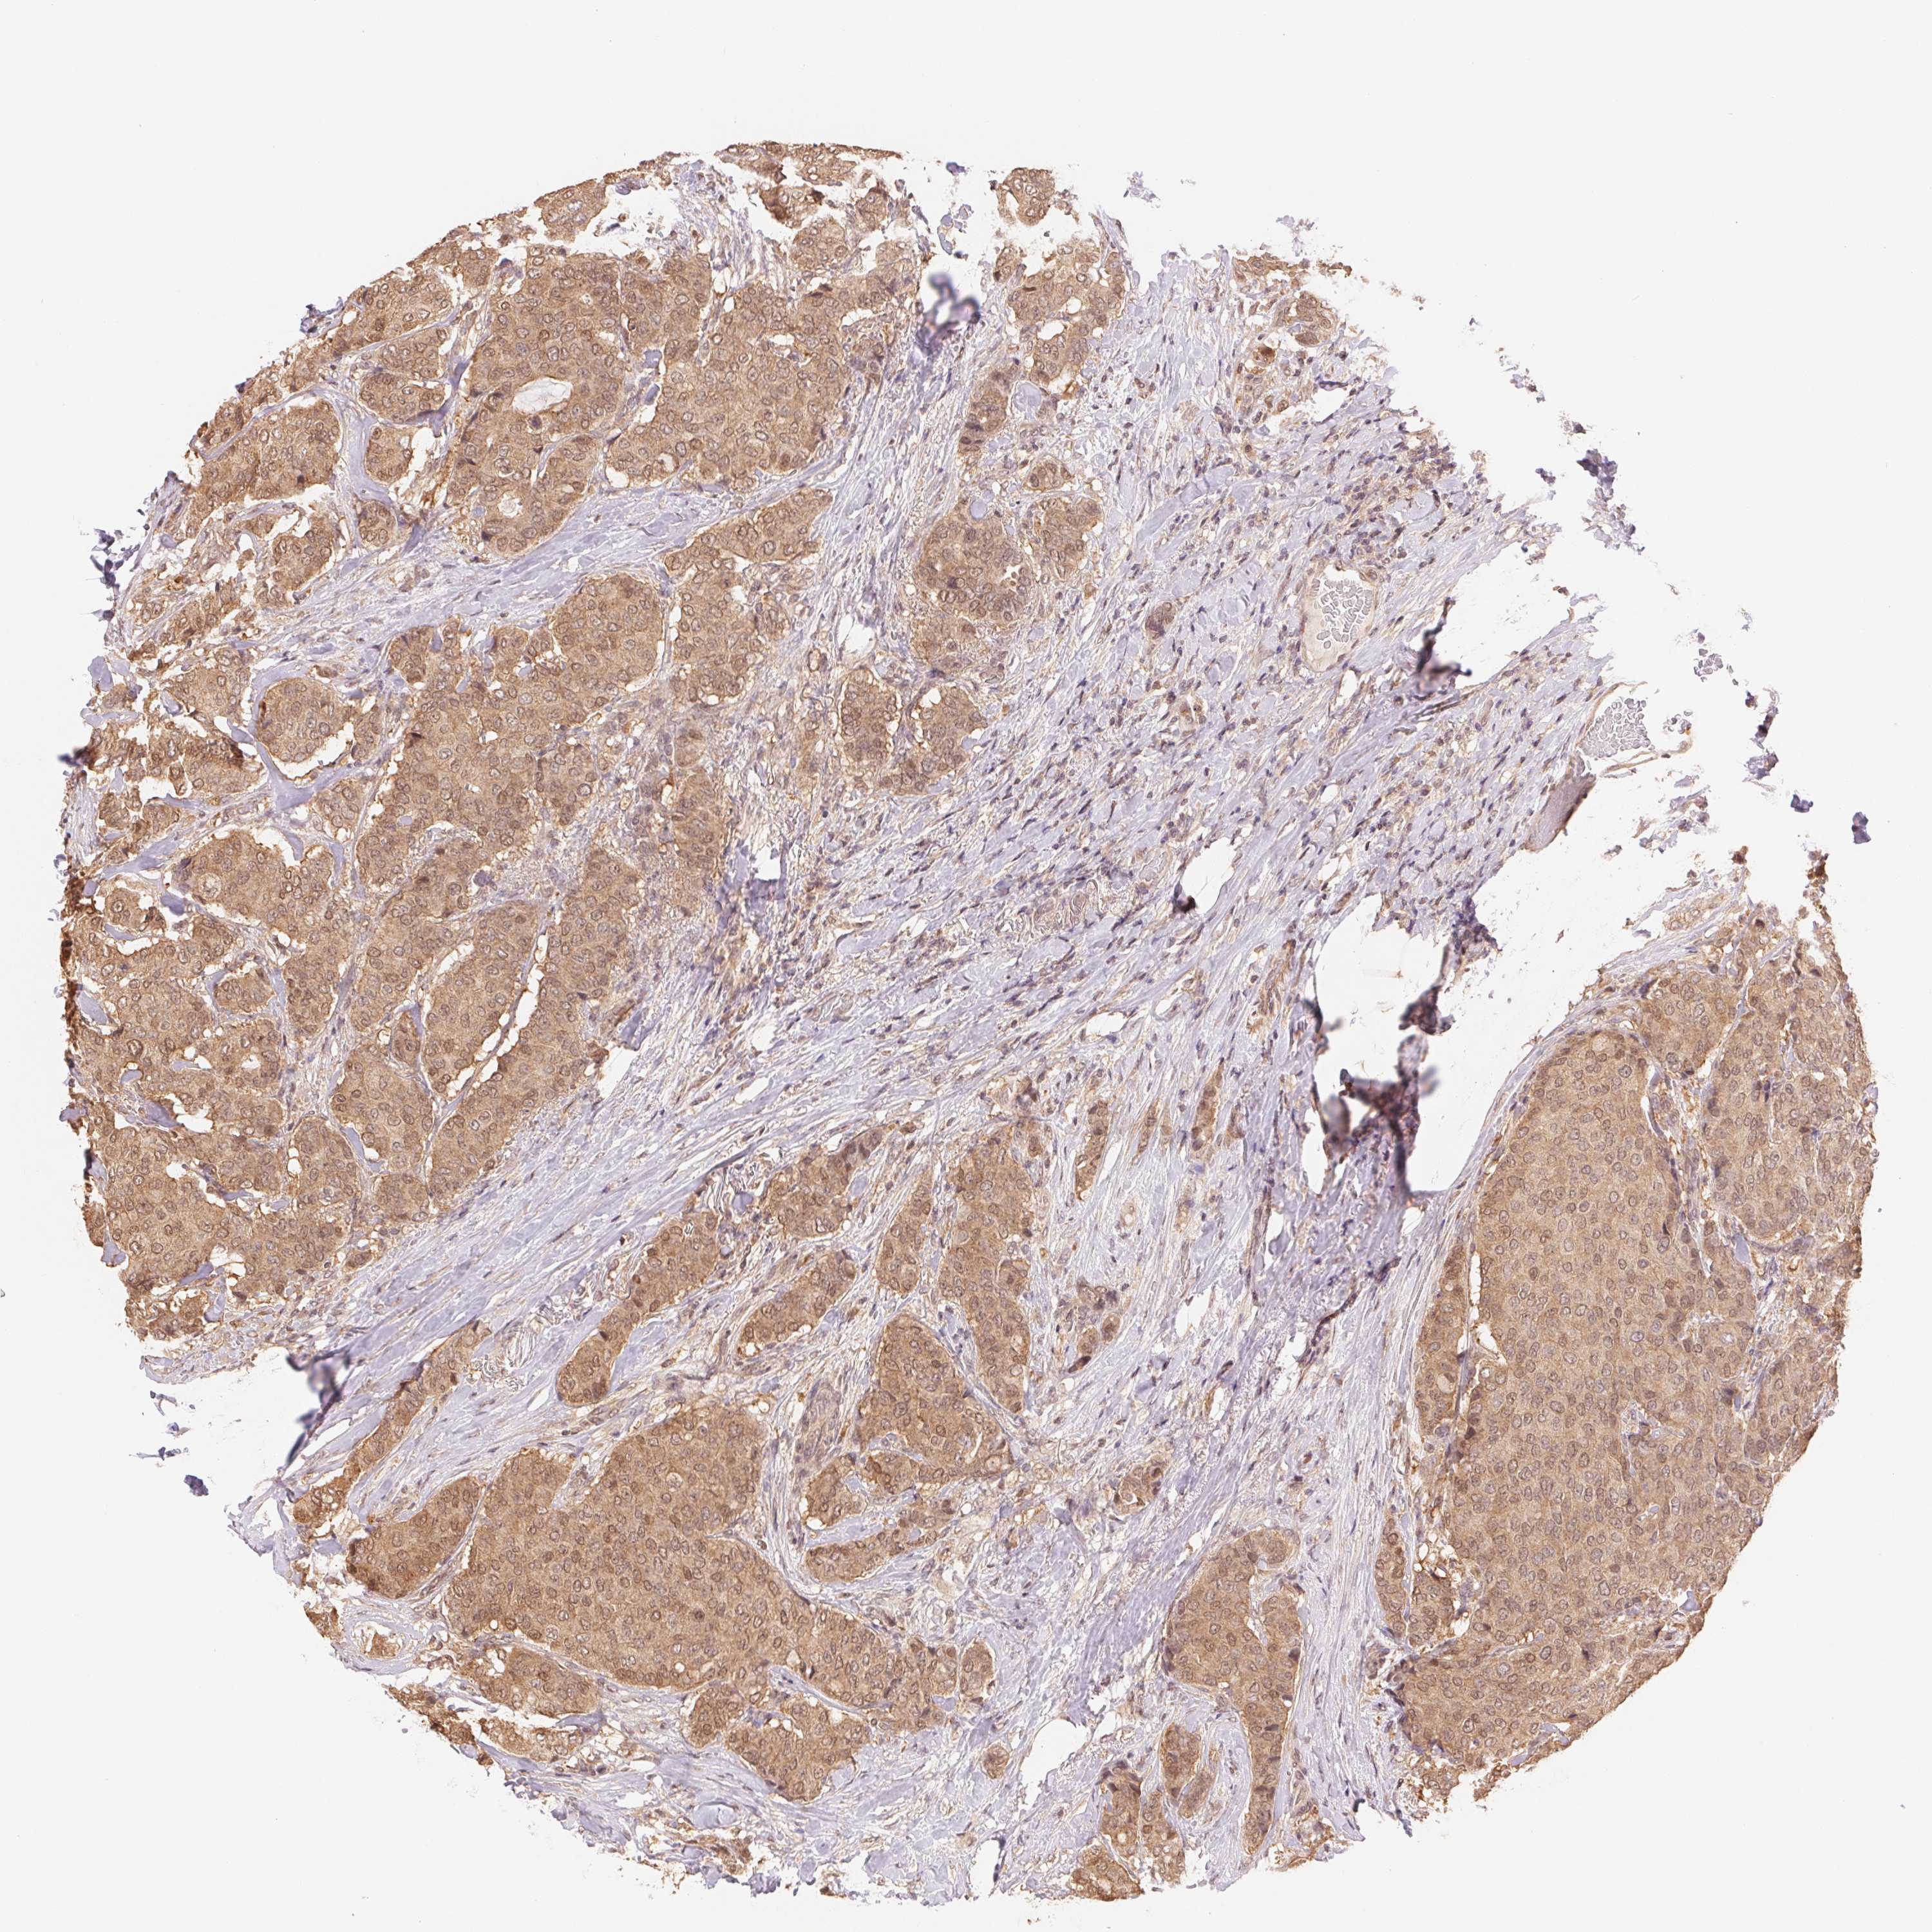

BRCA TCGA BRCA VALIDATION PROTEIN EXPRESSION

ANTIBODIES

AND

VALIDATION